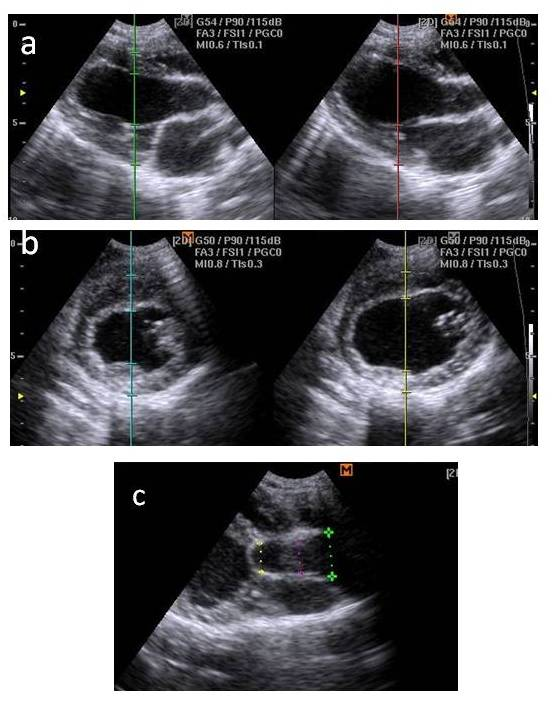

Trans-thoracic two dimensional and M-mode echocardiographic measurements were done prior to enrollment in the study (0 Time), and at 1.5, 3, 6 months following induction of aortic stenosis. Examination was done using a 4 MHz transducer coupled with Samsung Medison machine (Sonovet R3, Korea). The following measurements were recorded: left ventricular internal diameter in diastole (LVIDd), left ventricular internal diameter in systole (LVIDs), interventricularseptal thickening in diastole (IVSd), interventricularseptal thickening in systole (IVSs), left ventricular wall thickness in diastole (LVWd), and left ventricular wall thickness in systole (LVWs). The relative wall thickness (RWT), left ventricular mass (LVM) as well as the fractional shortening (FS) and the ejection fraction (EF) were calculated from the obtained measurements. The left atrial to the aortic root diameter (LA/Ao) ratio was also calculated. Doppler echocardiographic scan at the level of the aorta was done where the trans-stenosis gradient was recorded. All examinations and measurements were made by the leading edge technique following the criteria of the American Society of Echocardiography.

Echocardiographic measurements demonstrated that the diameter of the ascending aorta was decreased approximately 27.1 ± 2.1 % following banding. An increase in the ventricular wall thickness was evident starting from 1.5 month following banding of the ascending aorta, although this increase was not statistically significant at 1.5 month compared to baseline measurements. Significant increase in ventricular wall thickness as measured by left ventricular wall thickness in diastole (LVWd), left ventricular wall thickness in systole (LVWs), interventricularseptal thickening in diastole (IVSd), interventricularseptal thickening in systole (IVSs), relative wall thickness (RWT) and left ventricular mass (LVM)was recorded at 3 months. This increase in ventricular wall thickness was still apparent at 6 months echocardiographic measurement and was also confirmed by the post-mortum examination (Figure 1).

The ejection fraction (EF) as a measure of left ventricular systolic function was also decreased at 3 months (37.3 ± 1.5) and 6 months (29.3±2.1) following aortic stenosis compared to their baseline values (54.9 ± 4.6 %). The fractional shortening (FS) was decreased significantly at 6 months post- induction of stenosis.

Echocardiographic measurements and indices during the study are presented in (Table 2).